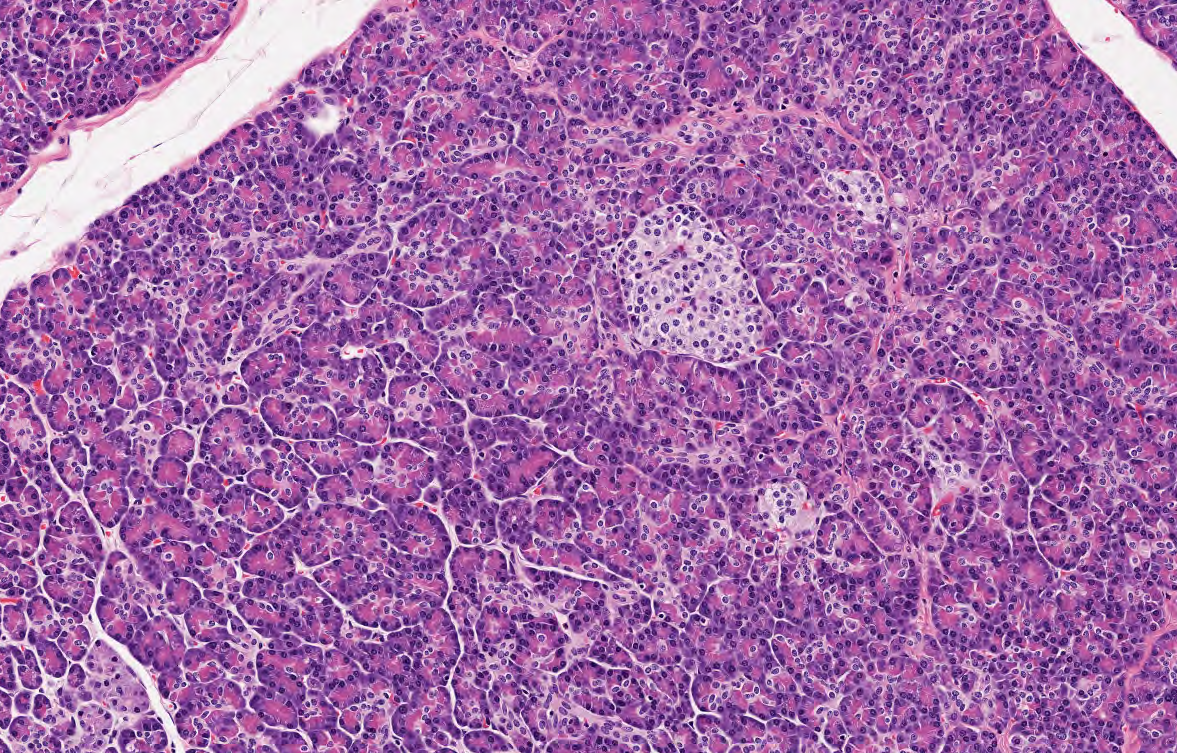

Páncreas cuenta con unidades funcionales encargadas de secretar enzimas digestivas, identifica el componente exocrino (poner foto histológica)

Acino pancreático